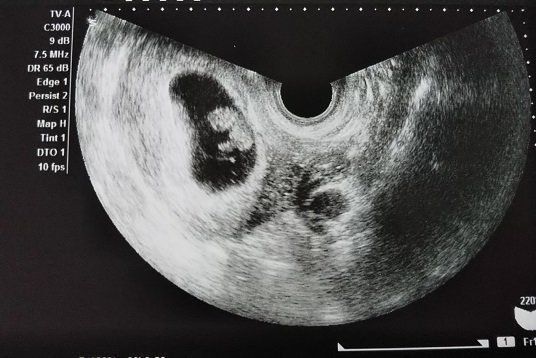

Chisatoさんの妊娠8週のエコー写真 手足が分かる。小さくてかわいい

さらに約10日後。赤ちゃんが少し人の形になってきていて、頭、手足がある様子が見てとれます。赤ちゃんの上部にある丸いものは、「卵黄嚢(らんおうのう)」だそうです。おなかの中がこんなに良く見えて、本当にびっくりでした。小さな心臓が元気に動いているのも確認できました。赤ちゃんの大きさは1.28cm。

私は、妊娠のかなり初期からつわりがあり、この頃は気分が悪くなるのが怖くて外食に行く勇気が出ませんでした。